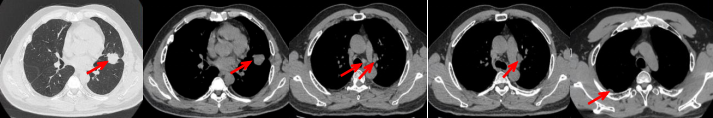

53岁男性,无吸烟饮酒史,脑血栓病史。2024年7月胸部CT:右肺下叶见一团块状软组织密度影,范围约10.8×9.0cm,边界不清,周围并见斑片状磨玻璃密度影,右肺下叶前底段支气管阻塞。纵隔及右肺门见肿大淋巴结影。考虑右肺下叶支气管肺癌。伴纵隔及右肺门淋巴结转移瘤,右下肺静脉瘤栓。2024.7.23行肺穿刺取病理:(肺)腺癌伴有神经内分泌分化。NGS基因检测:RET KIF5B exon15-RET exon12融合。PD-L1(克隆号28-8)TPS=90%。

治疗经过:2024.08开始口服赛普替尼(160mg,bid)。2024.09复查胸CT评效PR。2025.1复查胸CT:右肺下叶外基底段见一不规则形实性肿块,大小约94mm×87mm,边缘呈分叶状,其内密度不匀。右侧胸腔见少许水样密度影。评效PD,PFS=5个月。患者未同意再次组织活检,目前应用卡博替尼治疗,仍在随访中。治疗期间未出现毒性反应。

2024.08

2024.09评效PR

2025.01评效PD